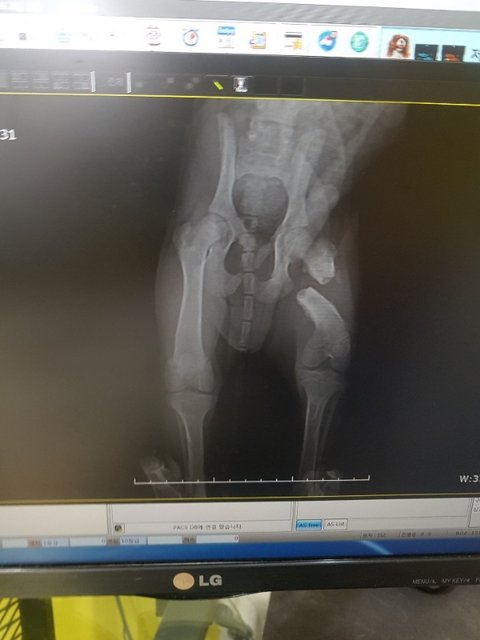

뒷다리 골절 아이소식 입니다

#김제보호소 #피부가안좋아요 #뒷다리골절 #4개월복동이 #수술해야합니다

금요일 두동강이 난 다리 수술을 앞두고 있습니다